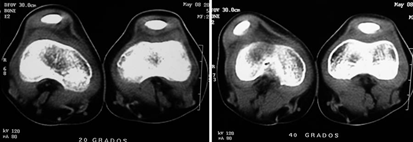

La tomografía es una herramienta importante en la determinación de la congruencia y/o subluxación patelo-femoral, para determinar hipoplasia de la tróclea y para identificar el grado de lateralización de la tuberosidad anterior de la tibia 17,18,23 . Figura 8.

Figura 8. La tomografía muestra que la rodilla derecha, a la izquierda en la figura, a 40º de flexión se subluxa, además se observa la displasia del surco o la tróclea. Fuente: Fotos propias del autor.